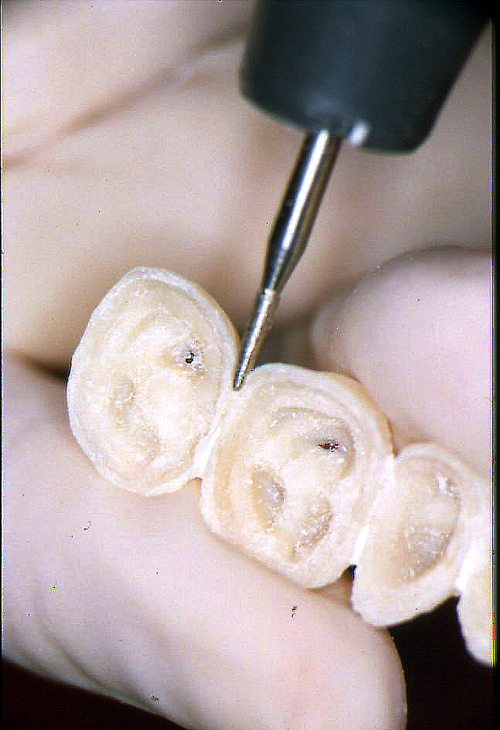

ABSTRACT El Bruxismo es una entidad patológica en la que concurren diferentes factores. Entre ellos el stress que conlleva consigo la vida moderna, constituye el Factor Predisponente sobre el que se ha abundado en innumerables tratamientos de tipo general, actuando sobre la psiquis y el comportamiento del individuo, ya sea con fármacos o bien mediante medios psicológicos. Sin embargo, como tantos desequilibrios provocados por el stress, confluyen siempre con un Factor Desencadenante, que en el caso del Bruxismo se encuentra en las desarmonías entre los componentes varios del Sistema Estomatognático. DESARROLLO Paciente varón, de 43 años, constitución atlética. A la inspección se observan desgastes oclusales que alcanzan la calidad de Facetas Parafuncionales, con dentina expuesta y empastes totalmente gastados y evidentes signos de falta de Disclusión Canina de ambos lados. Sobre dicho montaje se realiza un Encerado Progresivo de Diagnóstico, aportando en el mismo los elementos necesarios para obtener todos los principios básicos de una Oclusión Orgánica. FIG. 6 a 24 Una vez aprobado el fisiologismo de la oclusión en el articulador, se reproducen modelos de yeso con la nueva situación, y se estampa un SET UP en cada maxilar. FIG. 25/26 Procedemos entonces al tallado de las piezas correspondientes a la Guía Anterior, y rebasamos los estampados, creando en boca una nueva situación desoclusiva, que permanece en boca durante los pocos días que transcurren entre la primera y segunda visita de trabajo. FIG. 27/33 Ya abordando en esta segunda visita los sectores posteriores, tanto superiores como inferiores, tallamos siempre de manera supragingival, destacando la importancia vital de la forma obtenida en las provisionales, a las que abrimos plenamente las troneras para lograr una correcta higiene. FIG.34 a 43 FIG. 44 a 52 Efectuados los colados en oro y probados en boca, en el laboratorio se confecciona el bizcochado de la nueva Guía Anterior, la que puede o no copiarse de la Guía Anterior provisional, mediante la técnica denominada Trayectoria Funcionalmente Generada, que consiste en realizar en la platina del articulador un registro estereográfico sobre acrílico Duralay en polimerización. FIG. 57/58 Ajustados todos los detalles mediante esta técnica, se instala en boca en forma Provisional y se deja funcionando una semana o dos, al cabo de las cuales se chequean las disclusiones , los ajustes, la eficacia masticatoria, la carencia de sintomatología articular y muscular. FIG.59 a 63 PIE DE FOTO FIG.9 OBTENCIÓN DE LA GUÍA ANTERIOR FIG.10 Y 11 PITOMBOS. ALINEAC. TRIDIMENSIONAL FIG.12 PITOMBOS. DISCLUSIÓN DER. FIG.13 PITOMBOS. DISCLUSIÓN IZQ. FIG.14 WILSON INF. FIG.15 WILSON SUP. FIG.16 BOCA DE PEZ INF. FIG.17 BOCA DE PEZ SUP. FIG.18 VISTA OCLUSAL FIG.19 O.R.C. FIG.20 DISCLUSIÓN DERECHA FIG.21 CRESTAS TRIANG. INT. FIG.22 CRESTAS TRIANG. INT. FIG.23 CRESTAS TRIANG. INT. FIG 24 CRESTAS TRIANG. INT. FIG.59 DISCLUSIÓN IZQ. FIG.60 DISCLUSION IZQ. FIG.61 DISCLUSIÓN DER. FIG.62 DISCLUSION DER. FIG. 63 AJUSTE PERIFÉRICO